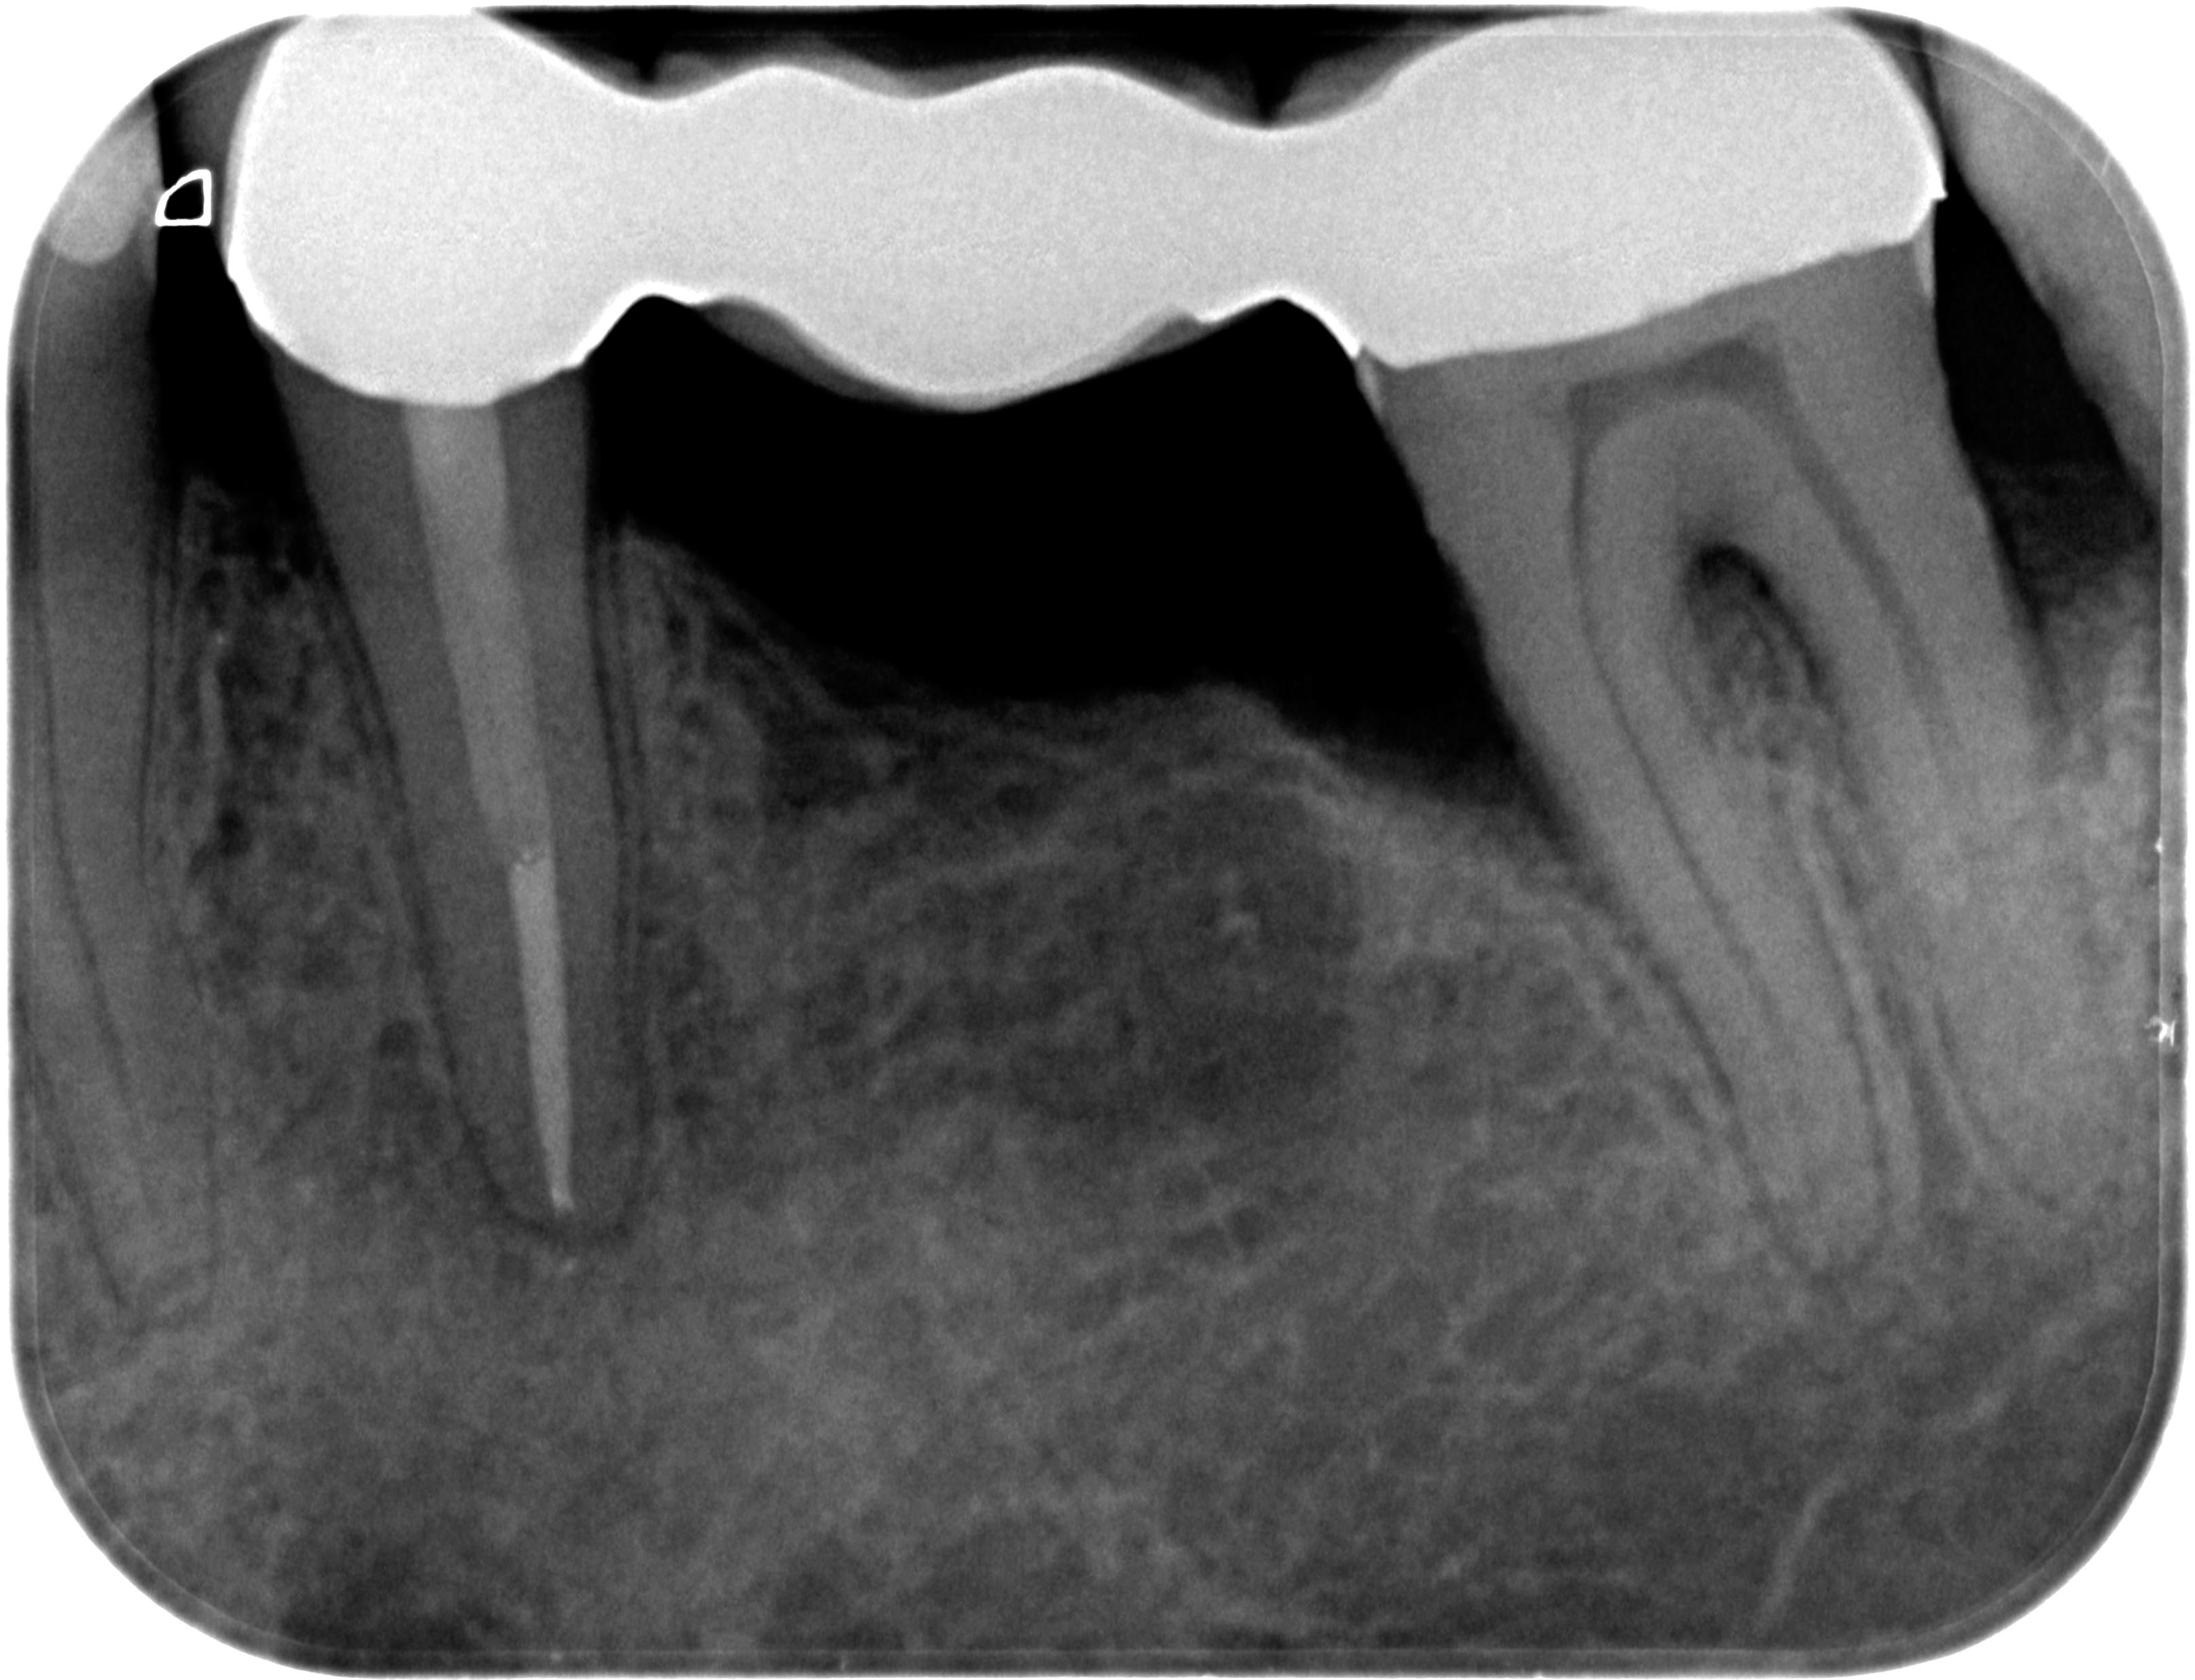

35 Zustand 30 Monate post WF Veröffentlicht 5. November 2013 am 3231 × 2473 in „Chapeau“ oder der Wirt und die Wette 35 Zustand 30 Monate post WF 2013